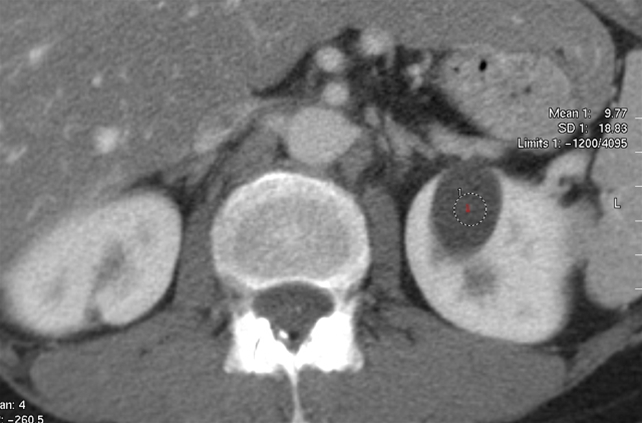

Nyrecyste (CT-scanning)

CT-scanning af nyrerne efter intravenøs indgift af røntgenkontraststof. Axial optagelse.

Der ses en velafgrænset, homogen, lav-attenuerende (mørk) cyste (1) fortil i højre nyre.